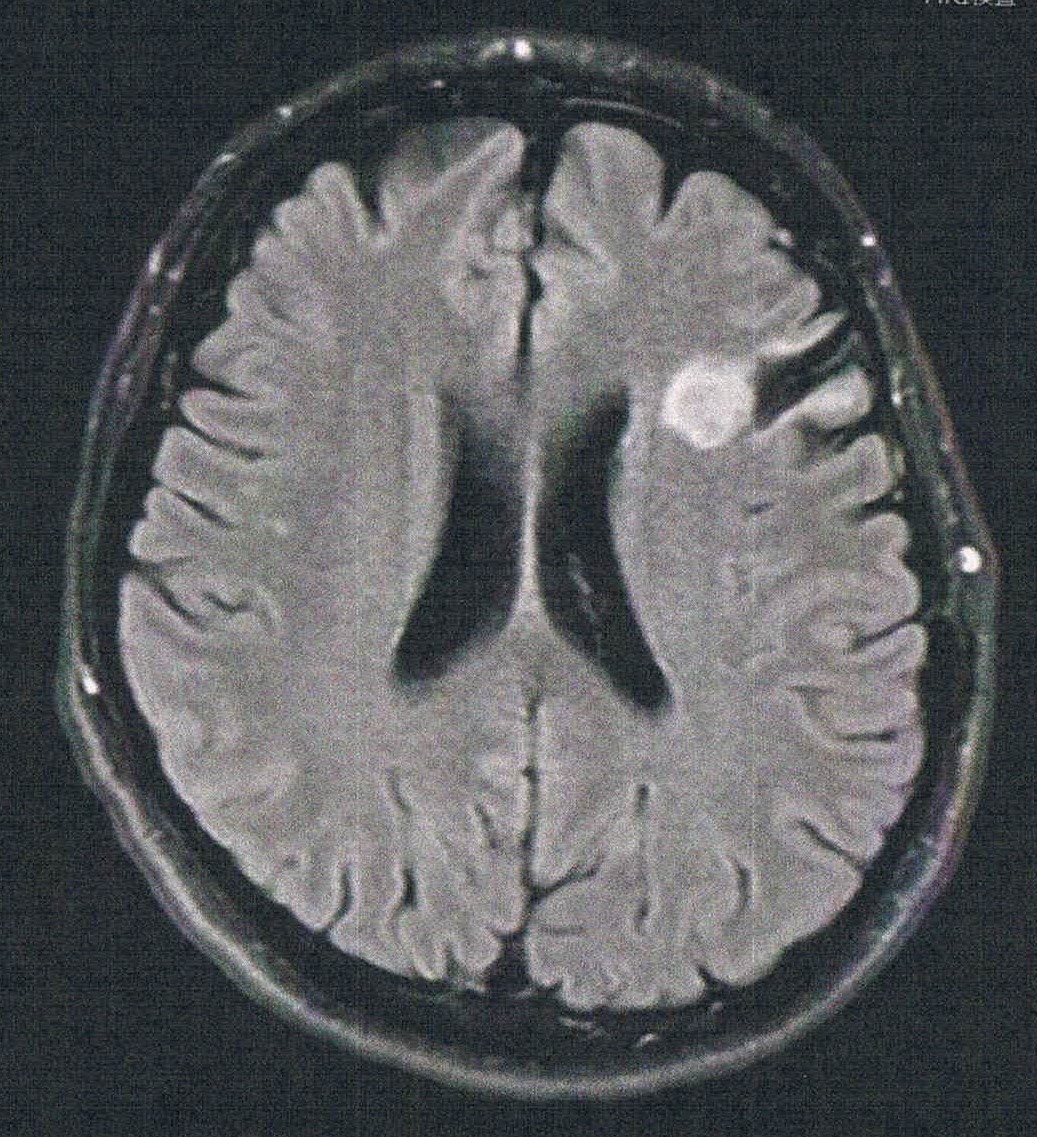

手術から8.5年が経過した。半年ごとの定期検査です。

- 悪性転化しやすい腫瘍の種類(びまん性星細胞腫グレード2)

- 造影剤を注射してMRI検査

- 1年前と比べて拡大は無し。造影剤でも問題なし。

- 言語野のほうへ広がるなら覚醒下手術で取る。

- 言語野から外れているようにも思われるが覚醒下でやってみないとわからない。2週間くらい失語の症状が出るかもしれない。